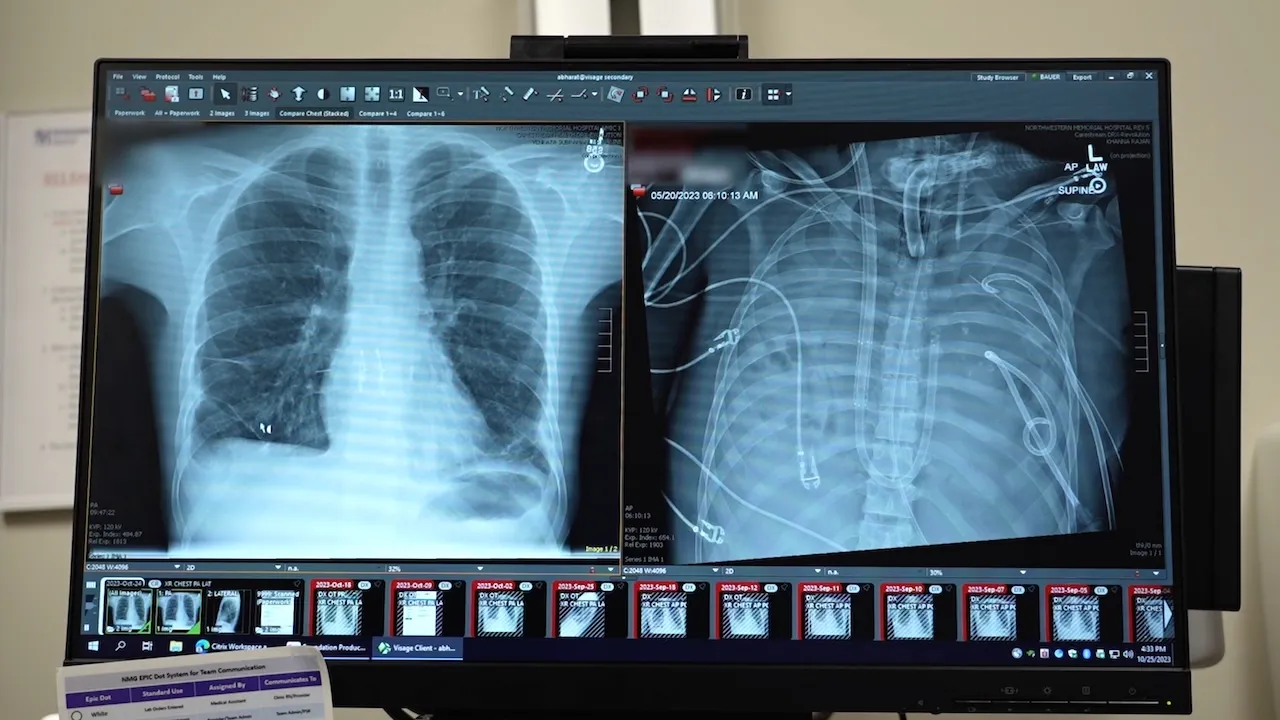

The patient’s new transplant is shown at left, and his old lungs are shown at right. “This technology allows us to ‘clean the slate’ by removing the infection, stabilizing the patient and bridging them to a successful transplant,” the lead surgeon said. (Northwestern Medicine)